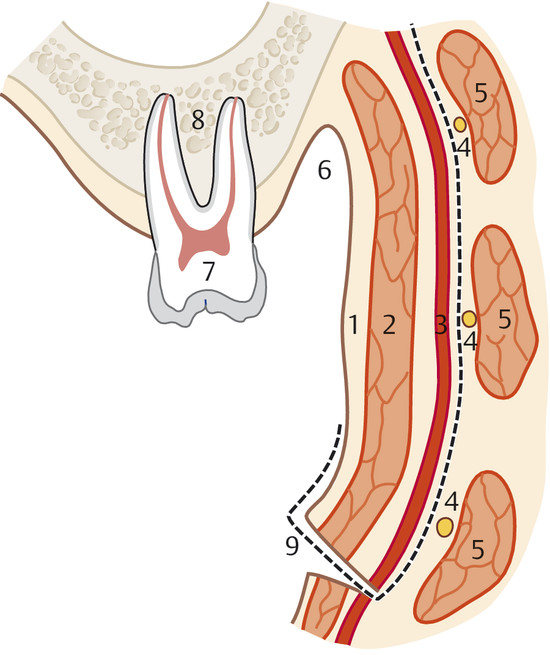

The FAMM flap is an intraoral cheek flap and includes the buccal mucosa, submucosa, buccinator muscle, and superficial layer of the orbicularis oris muscle (Fig. 18‑1). Superiorly based flaps are used for nasal septum perforations to maximize tissue length. Superiorly based FAMM flaps are pedicled on the angular artery and perfusion occurs through a retrograde flow. The facial artery is preserved on the entire length for the flap and kept attached to the buccinator muscle (Fig. 18‑2). The facial vein is usually not included in the flap as venous drainage is assured by a submucosal plexus. 24 The pivot point of flap is in the vicinity of the maxillary tuberosity or in the gingivolabial sulcus. The average width of the flap is 2.5 to 3 cm, and the pedicle base should be at least 1.5 cm to ensure adequate venous drainage. 17